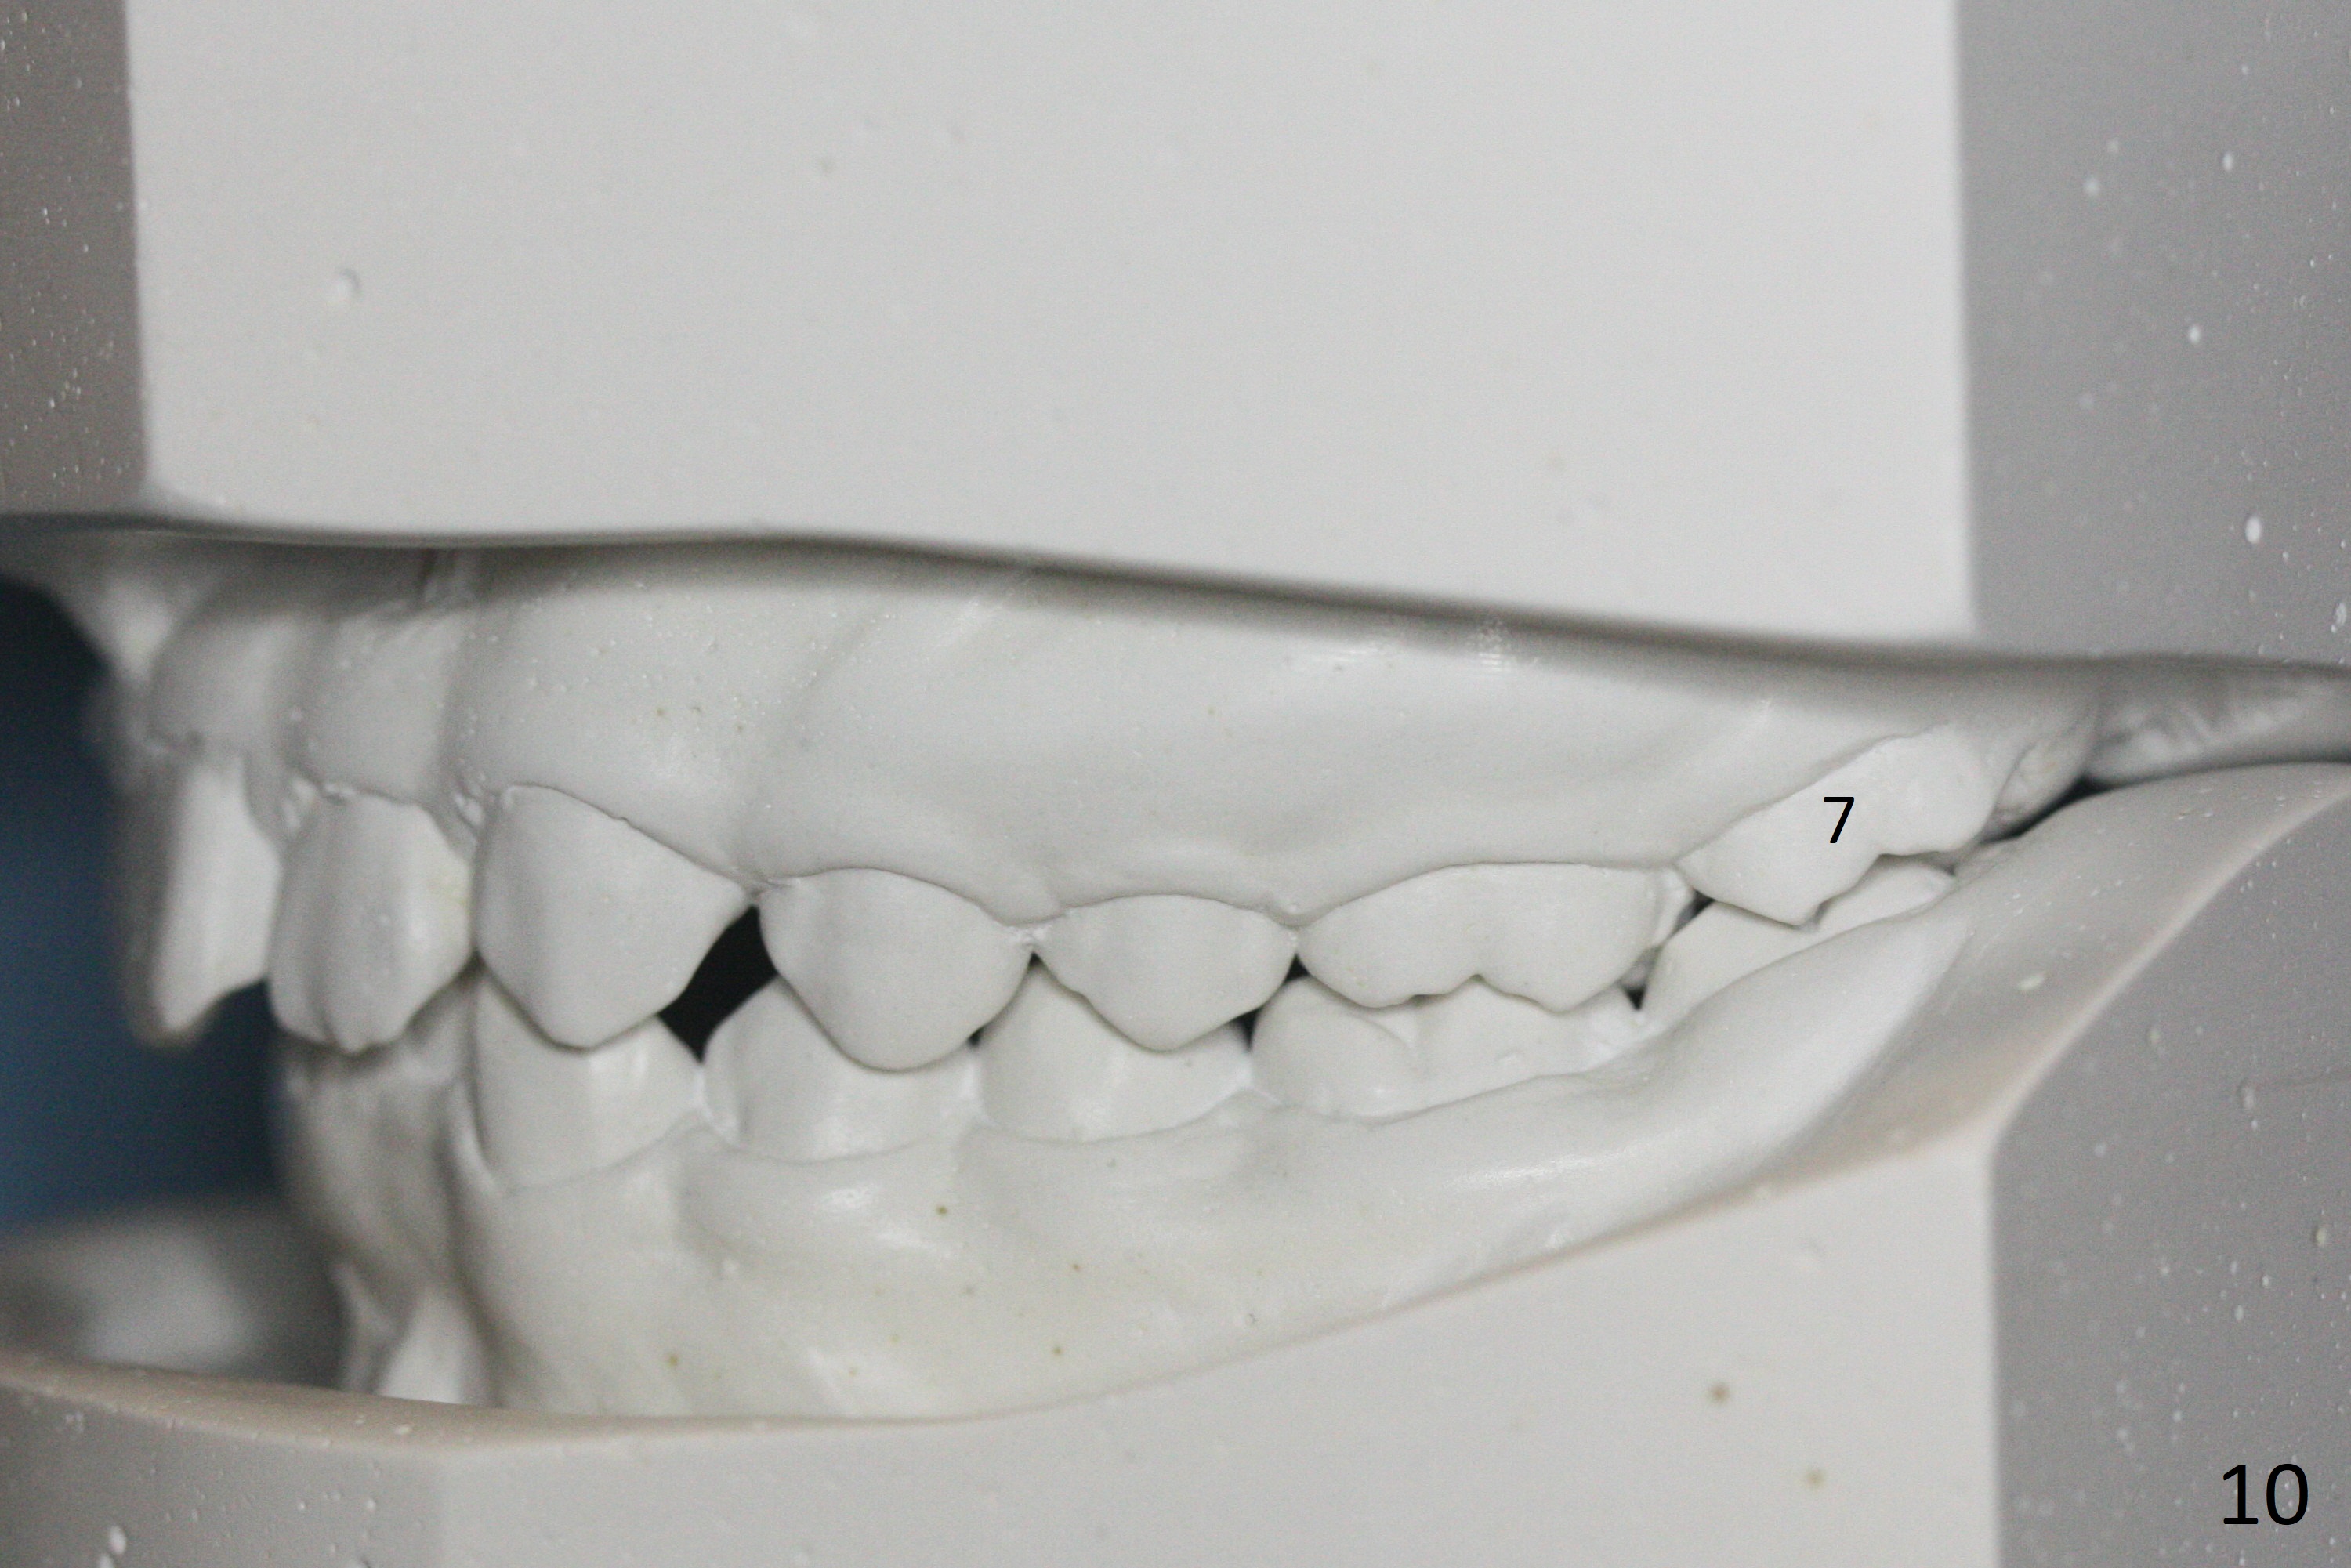

A 12-year-old woman has normal facial profile (Fig.1-6,12) and crowded dentition (7-11). Because of erupting 2nd molars (Fig.10,15), it is difficult to place rubber separators between U6/7. Copper ones are used instead (Fig.15 ^). Crowding and narrow arches (Fig.13,14) may be associated with the enlarged right Inferior Nasal Concha (Fig.15 *).